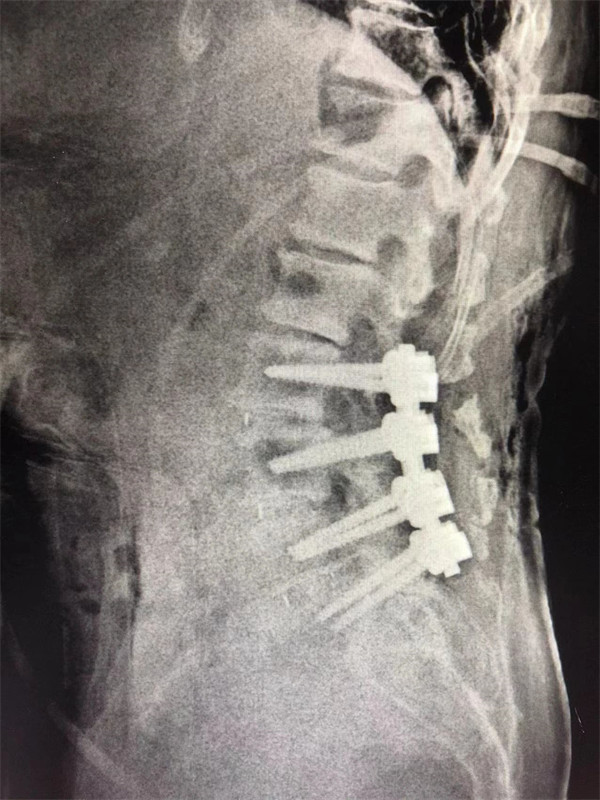

戈才華主任團隊討論病情及手術(shù)風(fēng)險,并與麻醉科醫(yī)生多次討論術(shù)中麻醉風(fēng)險,經(jīng)過詳盡周密的布置之后,最終給阿婆在全麻下進行腰3/4,4/5,腰5/骶1腰椎椎體間融合術(shù)。

術(shù)后阿婆腰痛伴雙下肢疼痛明顯緩解,術(shù)前疼得晚上睡不著覺的情況不再出現(xiàn)。阿婆和家屬連聲道謝,對醫(yī)生的治療技術(shù)和服務(wù)贊不絕口。

手術(shù)后↓